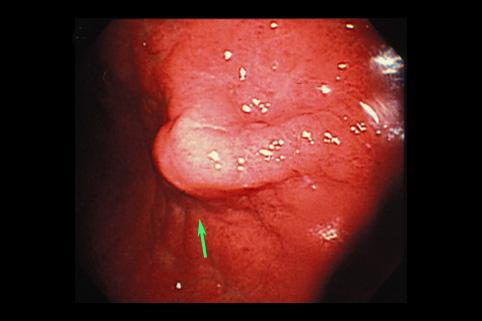

A case of gastric eosinophilic granuloma in the submucosa (most likely anisakis) which showed a submucosal tumor.

Gastrointinal Parasite/Anisakis

Location

Stomach/Antrum

Endoscopy

Size

15 - 19